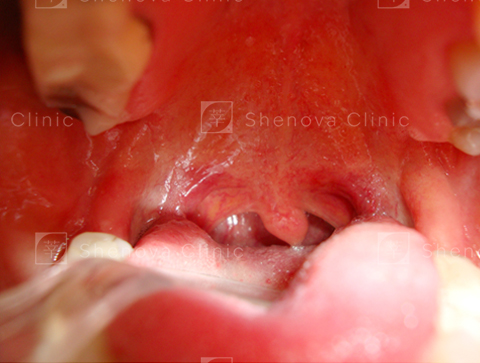

正常_軟硬顎、扁桃腺、懸壅垂位置圖01

正常

可見扁桃腺、軟顎、完整懸壅垂。